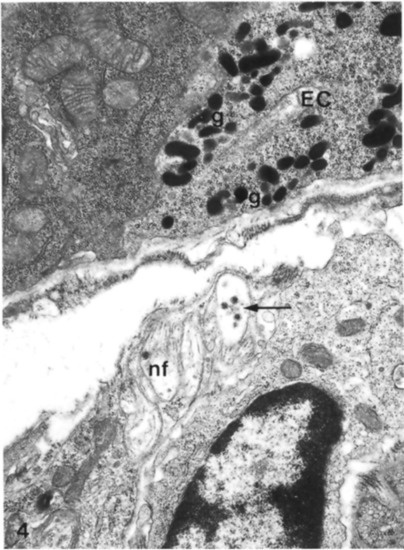

Figure 9. Base of an enterochromaffin cell fixed in glutaraldehyde and osmium tetroxide in which it is possible to see the presence of secretory granules containing clear and dense-cored vesicles, close to nonmyelinated nerve fibers. EC: enterochromaffin cell; nf: nonmyelinated nerve fibers; g: secretory granules; black arrows indicate dense-cored vesicles. X25.500. The Figure is obtained from Wade and Westfall, (1985). Reprinted by permission from Springer Nature Customer Service Centre GmbH: Springer Nature, Cell and Tissue Research (License Number 5232430326152, 19 January 2022) [33].

As can be seen in Figure 8, ECs showed a tuft of microvilli extending into the lumen of the GI tract, rough endoplasmic reticulum in the perinuclear region, secretory granules concentrated near the nucleus and at the base of the same cell. These granules were different in size and showed oblong, spherical, and biconcave shapes (Figure 9).

A very important finding was that ECs have bundles of nerve fibers below the epithelium basal lamina together with many fenestrated vessels. These considerations suggested that there were synaptic relationships between neuronal fibers and ECs even if, at the time, they had not been confirmed or previously reported in other studies [33].

The presence of vessels in proximity to ECs has supported the idea that their secretory products have endocrine functions. Their products were transported by the blood stream to their site of action and finally, when a cell secretes a product, it normally causes a local or paracrine function with potent effects on intestinal tissues [33].